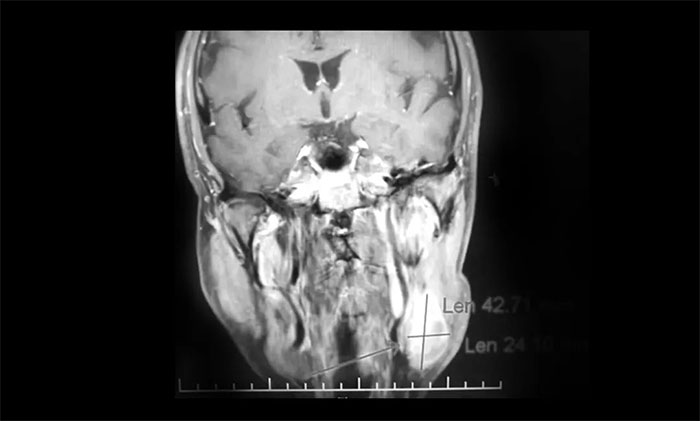

一位64岁男性患者,因“左颈部淋巴结肿大伴鼻出血半月”在外院行鼻咽镜活检病理结合影像学检查,提示鼻咽癌可能。为寻求进一步治疗近期来到我院。查MRI:左侧鼻咽部实性占位性病变,考虑恶性肿瘤,侵及左侧咽旁间隙;左侧下颌腺区及颈部淋巴结异常肿大(转移可能)。

▲ 入院MRI影像